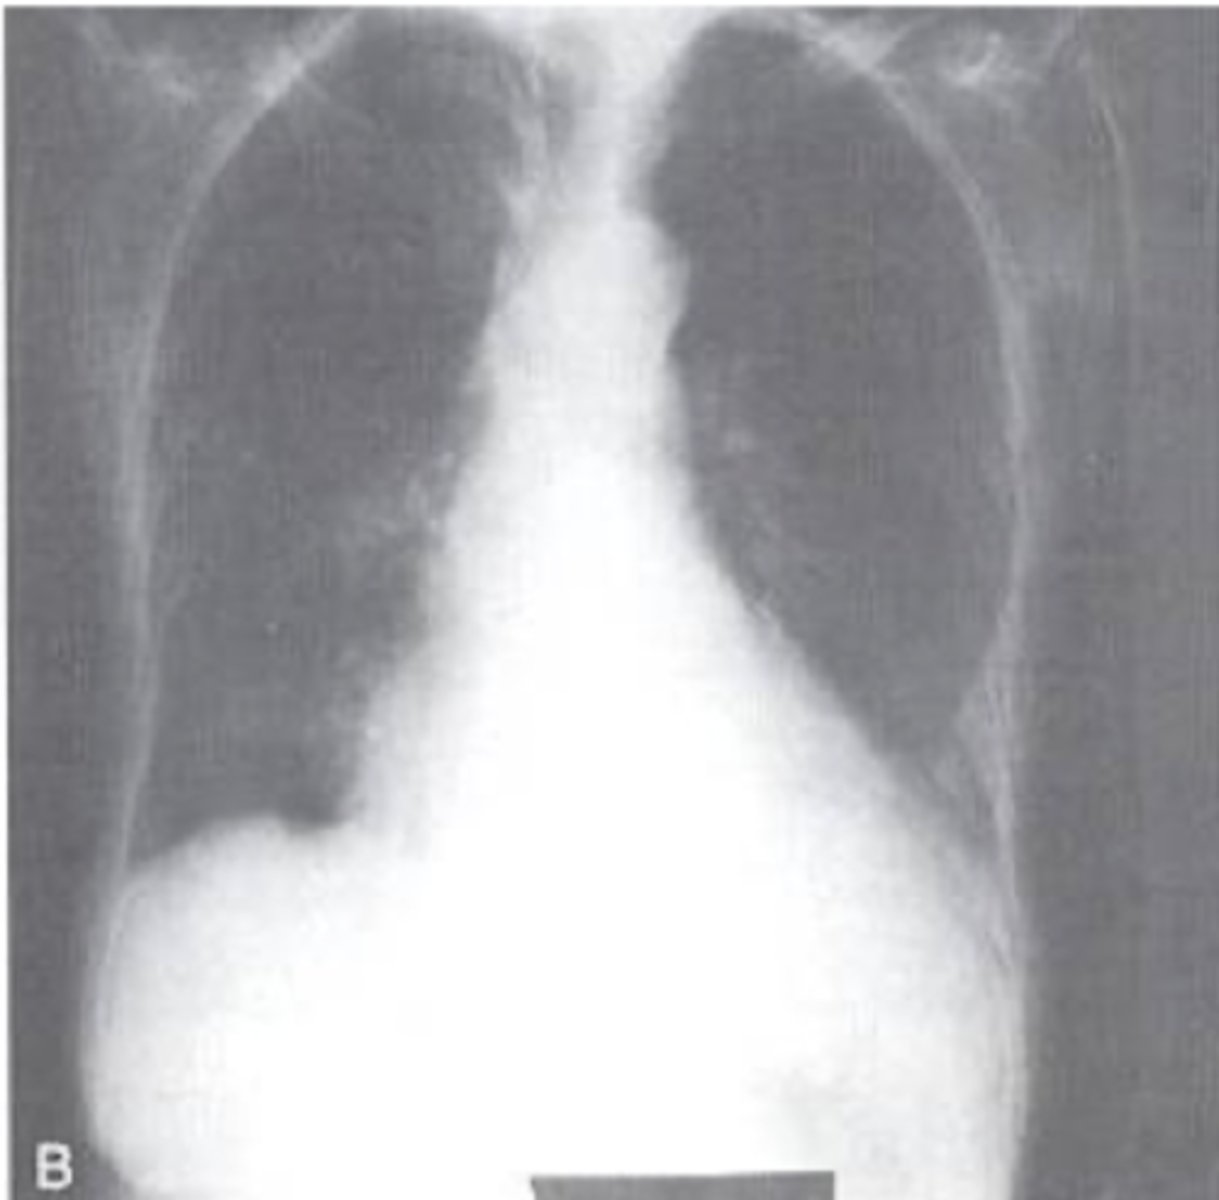

Left is T1, Right is T2

Which side is T1 which side is T2?